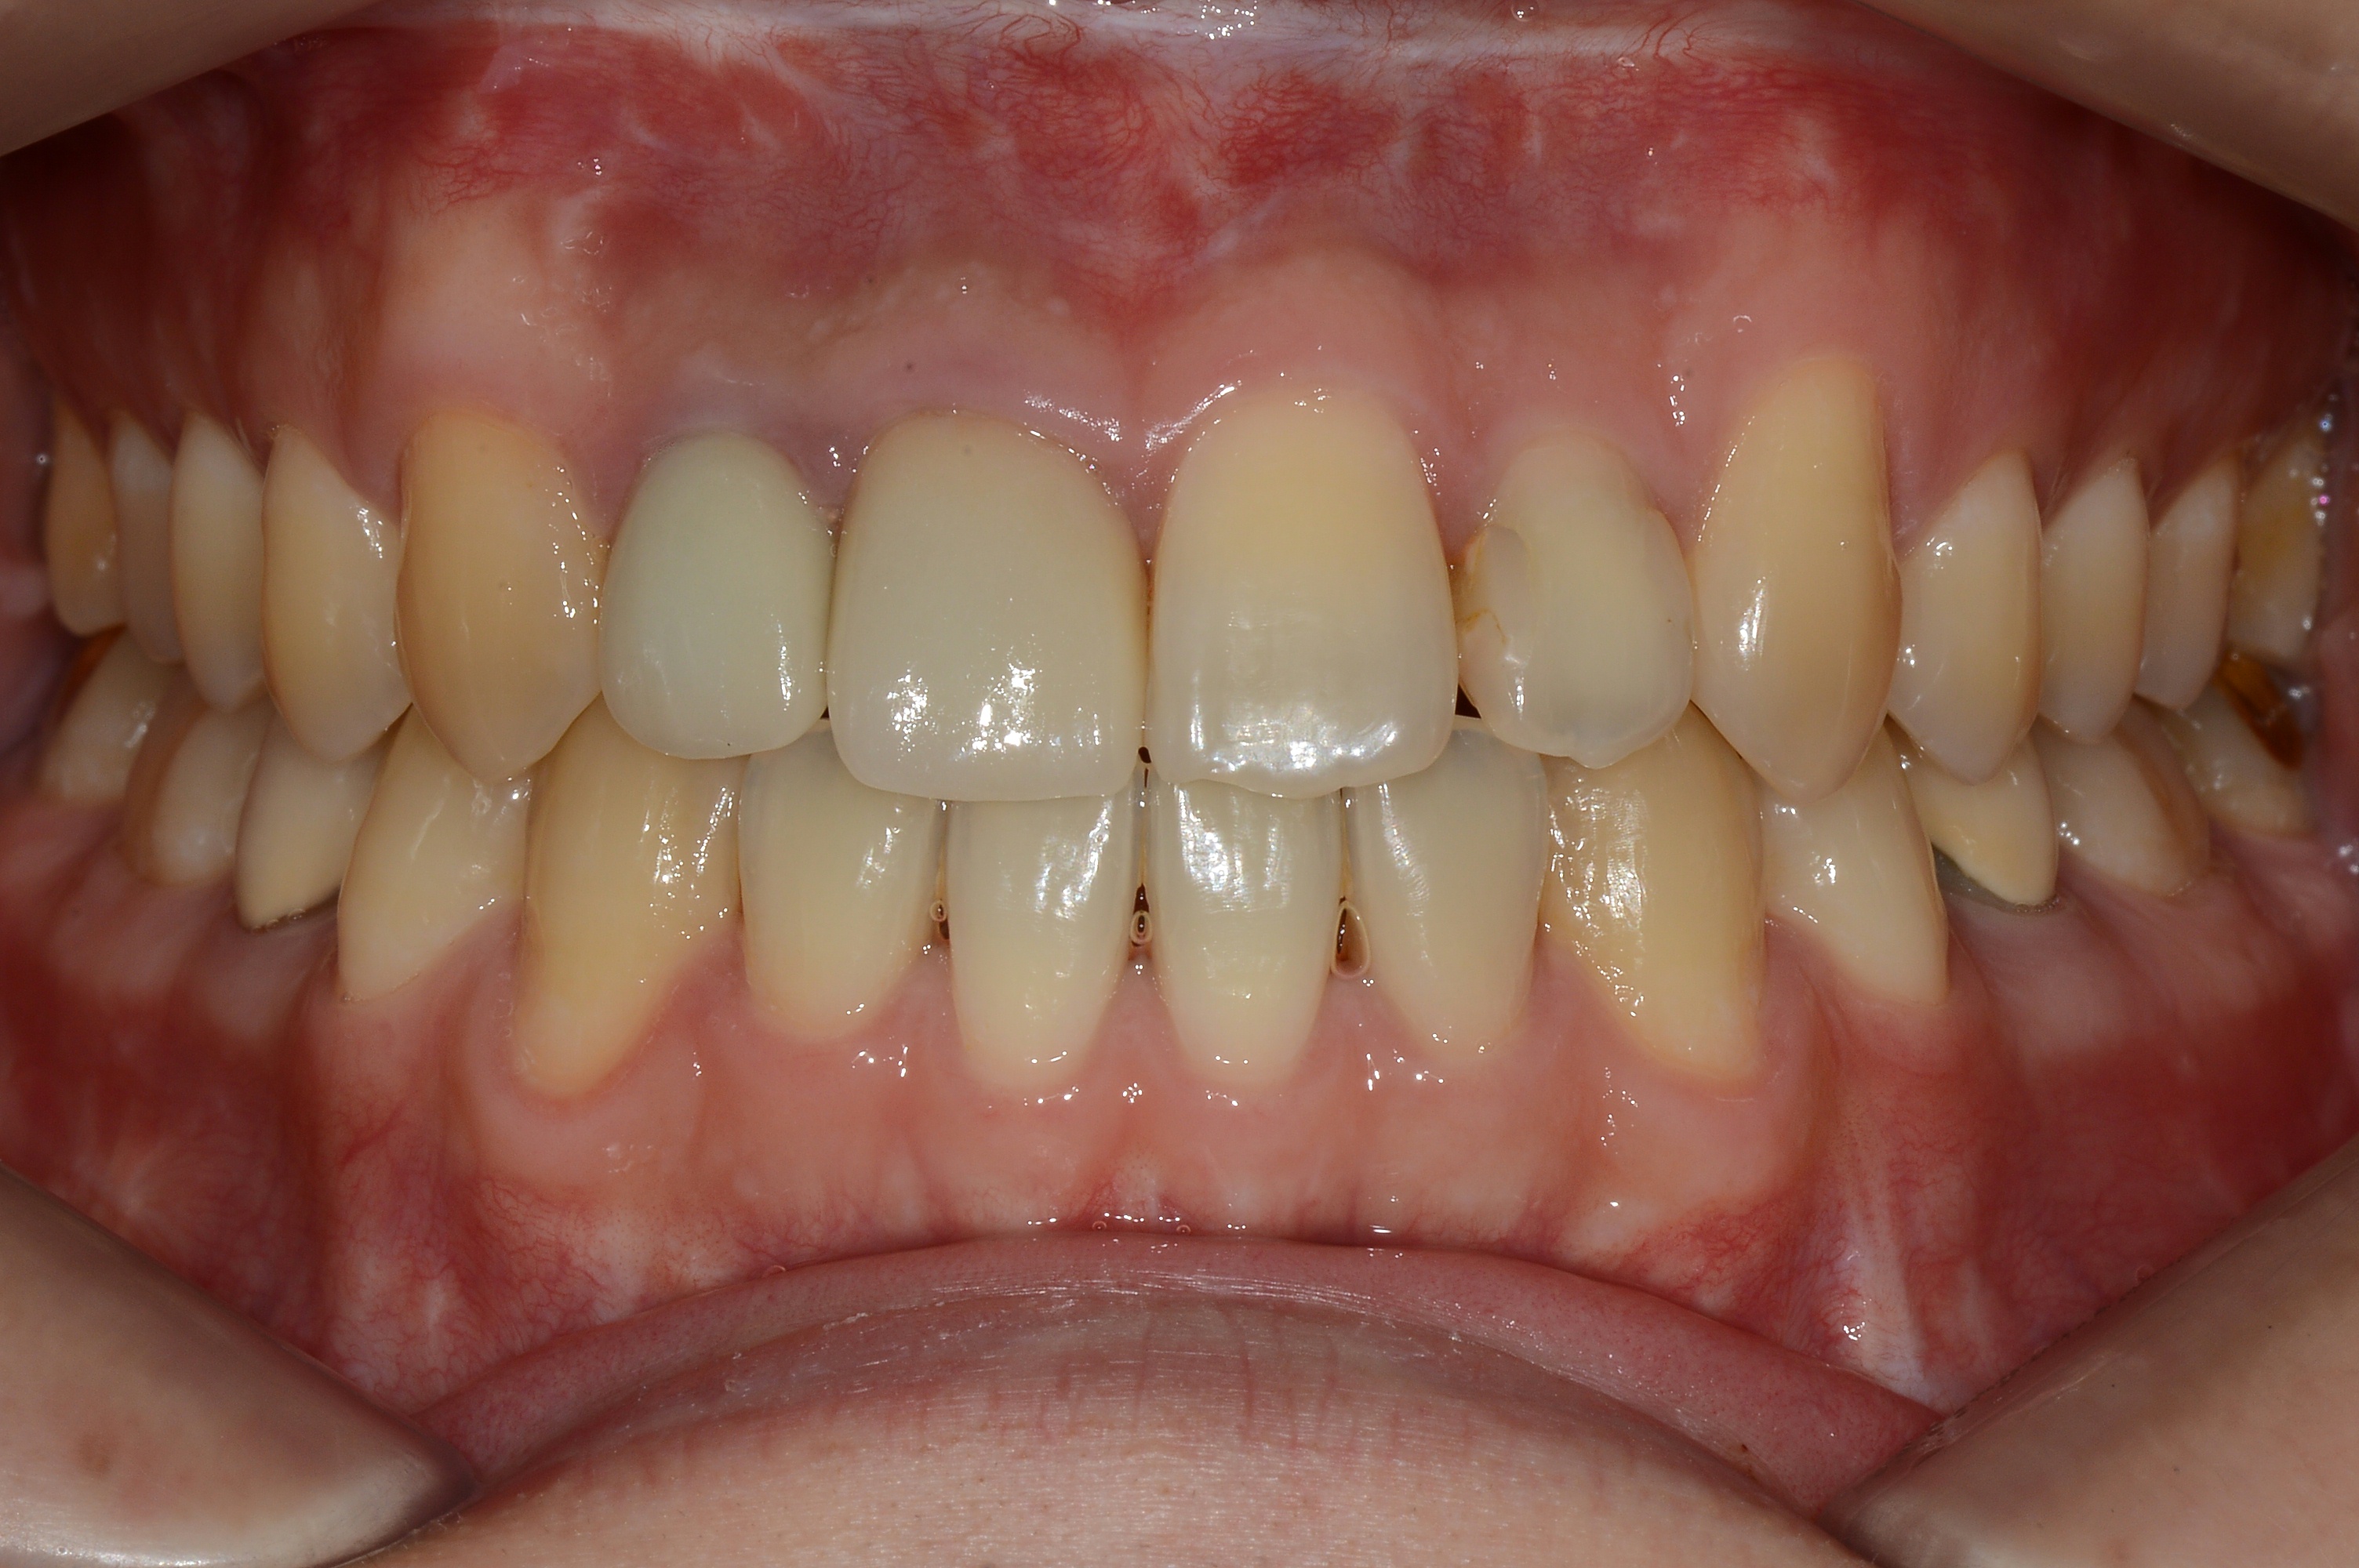

치료 후 사진입니다.